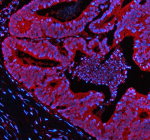

IF analysis of NEK9 using anti-NEK9 antibody (red). NEK9 was detected in a paraffin-embedded section of human colon cancer tissue. Heat mediated antigen retrieval was performed in EDTA buffer (pH 8.0, epitope retrieval solution). The tissue section was blocked with 10% goat serum. The tissue section was then incubated with 5 ug/ml rabbit anti-NEK9 antibody overnight at 4oC. Cy3 Conjugated Goat Anti-Rabbit IgG was used as secondary antibody at 1:500 dilution and incubated for 30 minutes at 37oC. The section was counterstained with DAPI (blue). Visualize using a fluorescence microscope and filter sets appropriate for the label used.